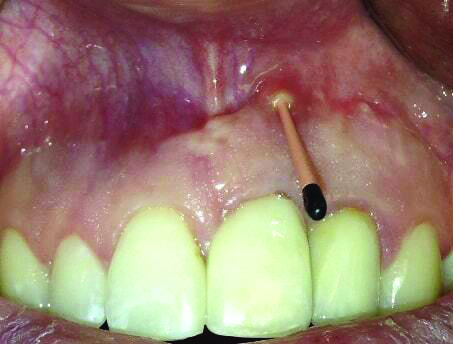

Fig 1 and Fig 2. Case 1: Initial clinical presentation with gutta-percha placed in the apical fistula of tooth No. 9 (Fig 1); radiograph showing gutta-percha point leading to the periapical lesion (Fig 2).

Patient 1: A 30-year-old female patient with an unremarkable medical history presented with implant No. 9 exhibiting retrograde peri-implantitis. Tooth No. 9 had been replaced with the implant 8 years prior because of a history of trauma and failed root canal treatment. The implant exhibited a periapical radiolucency with the sinus tract tracing to the apex of implant No. 9 (Figure 1 and Figure 2). The patient had a high smile line with longer clinical crowns at Nos. 9 and 10 compared with Nos. 7 and 8 (Figure 1 and Figure 2).